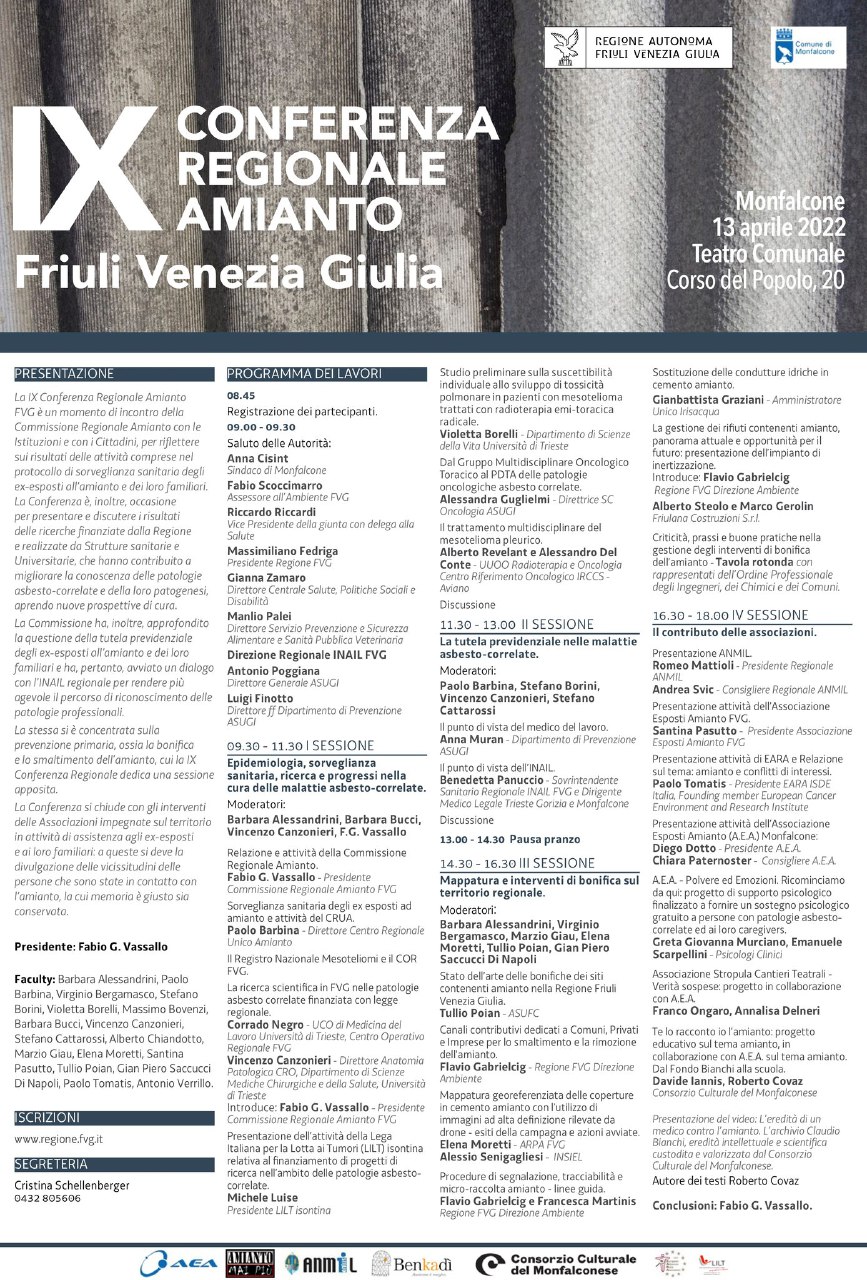

Monfalcone

Monfalcone

Monfalcone

L'Associazione LILT, che si distingue per l'impegno a livello nazionale nella lotta contro i tumori attraverso campagne informative, ricerca scientifica, pubblicazioni di opuscoli, educazione sanitaria, interventi nelle scuole, eventi, esami e controlli periodici effettuabili presso gli ambulatori delle Sezioni Provinciali, oltre[...] Vai alla notizia

Monfalcone

Tra le iniziative che LILT ha portato avanti, il 10 ottobre alle ore 20.30 a Monfalcone si terrà una serata culturale gratuita al Teatro Comunale di Monfalcone, organizzata dal Comune e da LILT Isontina in ricordo del maestro Aldo Policardi. Vai all'evento